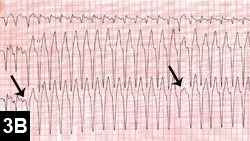

The ECG characteristics of VT include wide and bizarre QRS complexes without any associated P waves in addition to tachycardia (heart rate, >180 bpm; Figure 3A).

Although no treatment has been proven to prevent sudden death in patients with VT, antiarrhythmic therapy is used especially if the patient is a breed predisposed to sudden death, the patient is symptomatic, and/or malignant characteristics are present on VT (eg, rapid heart rate [>180 bpm]) or R-on-T or polymorphic QRS complexes are present (Figure 3B). The most common medications used for ventricular arrhythmias include IV lidocaine (acutely administered), sotalol, and PO mexiletine. Sotalol and mexiletine can be compounded into a liquid formulation for titration of doses, if necessary. In cases of significant systolic dysfunction, mexiletine can be used at 4 to 8 mg/kg PO q8h. This same dose can be added to sotalol when ventricular arrhythmias persist despite administration of maximal doses of sotalol. Other medication combinations (amiodarone, flecainide, propafenone, procainamide) may be needed for patients that are refractory to conventional therapy. Implantable defibrillators are occasionally required to treat high-risk patients.

FIGURE 3A

Six-lead ECG in a boxer with arrhythmogenic right ventricular cardiomyopathy. There is monomorphic VT at an extremely fast rate of ~350 bpm (paper speed, 50 mm/sec; sensitivity, 10 mm/mV).